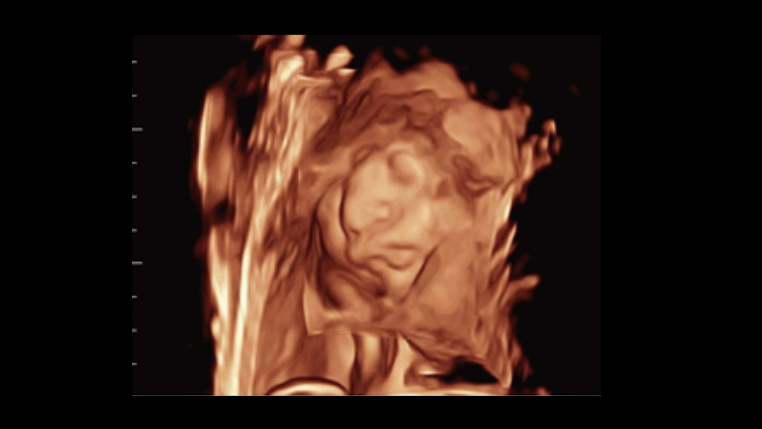

Comprehensive upgrading on iLive to significantly improve the detailed resolution as well as anatomical realism. Hyaline is a new rendering method that dynamically applies transparency to rendered structures for a more comprehensive view of anatomy, therefore better displaying internal anatomy from a solid surface.